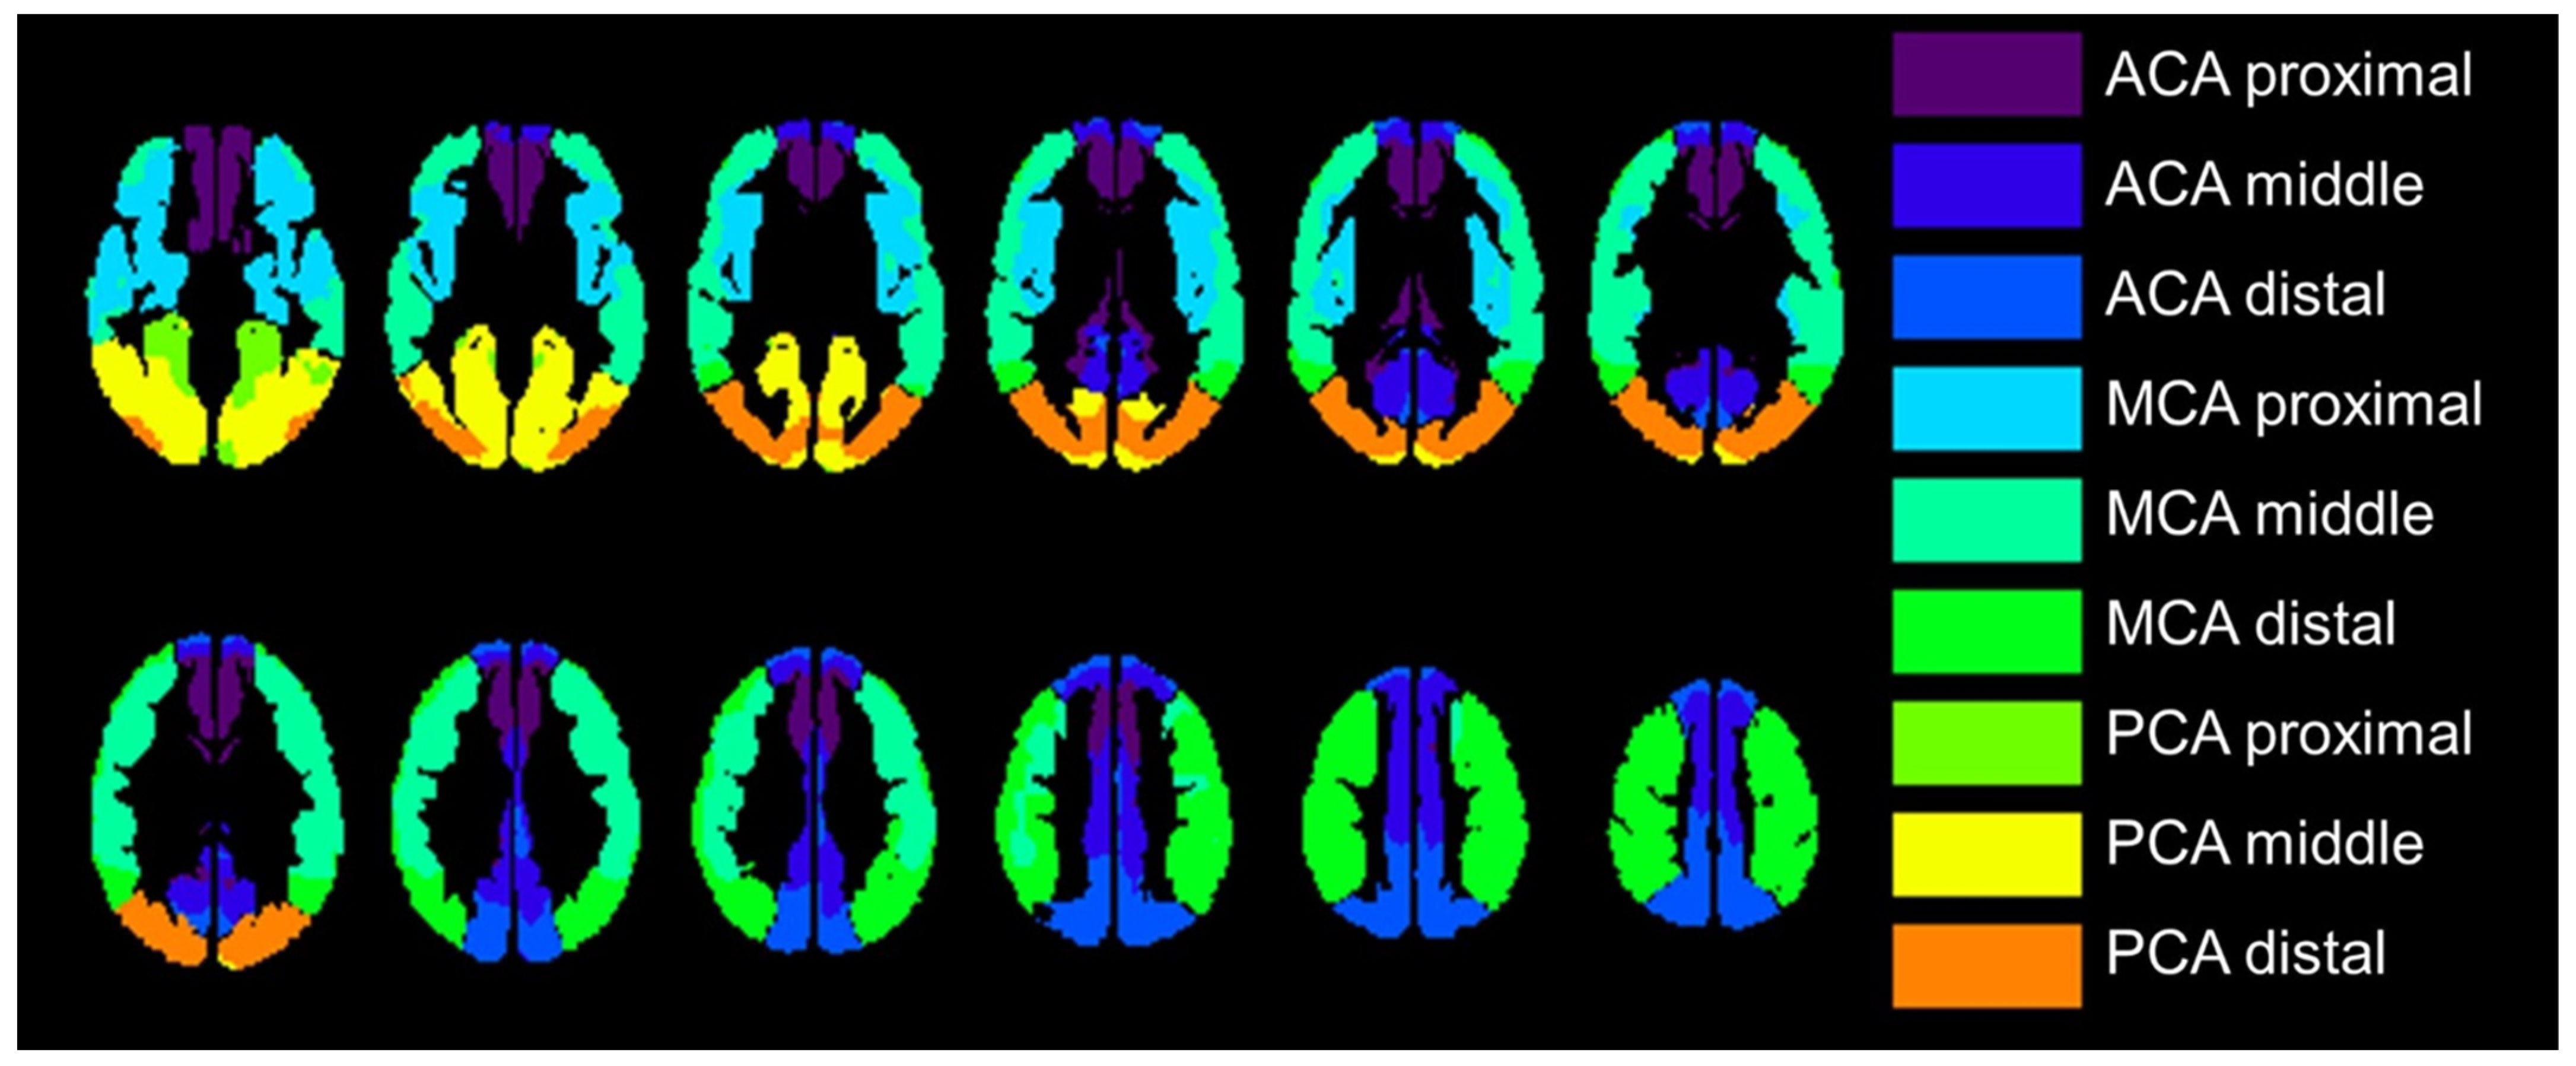

The transit time-based ROI value extraction was used in the comparison between PET and ASL parametric images, which were categorized into 18 regions: the left and right proximal, intermediate, and distal regions of each of the major anterior cerebral artery (ACA), middle cerebral artery (MCA), and the posterior cerebral artery (PCA) territories, which is previously reported and available in MNI standard space [26]. Figure 2 shows transit time-based ROIs. Relative CBF value in each ROI was calculated relative to the whole gray mask CBF value in each PET and ASL-CBF. We selected the MCA ROIs when we compared ROIs with affected and nonaffected cerebral flow based on the PET-CVR less than mean value of 30%.

Figure 2.

The regions of interest (ROI) were placed proximal, middle, and distal to the major vascular territories with structures located in the deep gray matter not included (e.g., basal ganglia and thalamus); 18 regions were measured per case. ACA, anterior cerebral artery; MCA, middle cerebral artery; PCA, posterior cerebral artery.